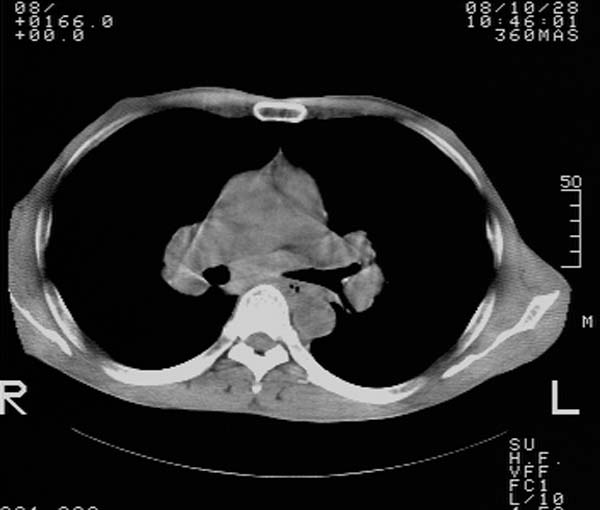

m,65y。半年前发现颈小结节,逐渐增多增大,现双侧耳后、颌下及颈部表浅淋巴肿大。胸片示双肺门增大。外院曾穿刺诊断为淋巴结核。在我科作胸腹部ct,我们觉得外院病检有误。现将图像上传请战友讨论。

纵隔内及腹膜后广泛淋巴结肿大,脾大,肝内似可见低密度影,结合病史半年前发现颈小结节,逐渐增多增大,现双侧耳后、颌下及颈部表浅淋巴肿大。考虑淋巴瘤。

纵隔,双肺门腹膜后多发淋巴结重大,非融合,肝脾轻度肿大,双肺野弥漫性小结节;考虑淋巴瘤,结节病可能性

纵隔内,双肺门、腋窝及腹膜后多发肿大淋巴结影,肺内小结节影,肝脾体积增大,支持淋巴瘤。肝内多发低密度影,考虑小囊肿。

纵隔内,双肺门、腹膜后多发肿大淋巴结影及颈部淋巴结肿大,肝脾体积大.结合临床,淋巴瘤可能性大。